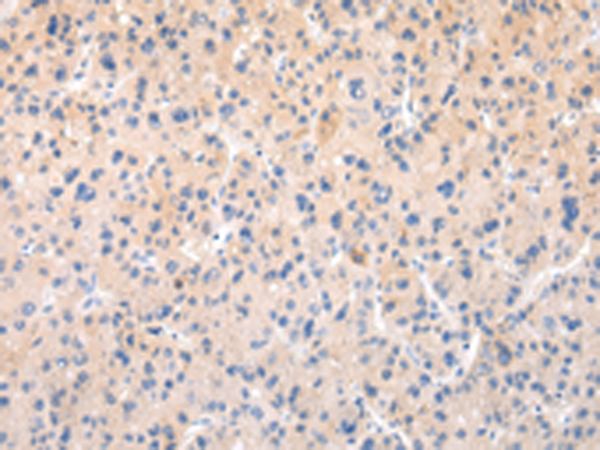

分类: 科研抗体货号: P12470别名: MRP; ABCC; GS-X; MRP1; ABC29应用: WB,IHC反应种属: Human